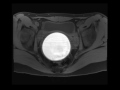

Hematometrocolpos

Young patient with an enlarging pelvic mass. MR images demonstrate the uterus, cervix, and vagina distended with T1 and T2 hyperintense blood products, with no apparent enhancement on the post-gadolinium images. This is a classic appearance of hematometrocolpos, in this case secondary to an imperforate hymen.